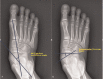

Idiopathic flatfoot is common in infants and children, and patients with this condition are frequently referred to pediatric orthopedic clinics. Flatfoot is a physiologic process, and that the arch of the foot elevates spontaneously in most children during the first decade of life. To achieve a consensus as the rate of spontaneous improvement of flatfoot, the present study aimed to estimate the rate of spontaneous improvement of flatfoot and to analyze correlating factors.We reviewed the records of patients examined between May 2013 and May 2019 so as to identify those factors associated with idiopathic flatfoot below 12 years of age. We included patients with who had been followed for >6 months, and those for whom ≥2 (anteroposterior and lateral) weight-bearing bilateral radiographs of the foot had been obtained. The progression rates of the anteroposterior (AP) talo-first metatarsal angle, talonavicular coverage angle, lateral talo-first metatarsal angle, and calcaneal pitch angle were adjusted by multiple factors using a linear mixed model, with sex, body mass index, and Achilles tendon contracture as the fixed effects and age and each subject as the random effects.We found that 4 of the radiographic measurements improved as patients grew older. The AP talo-first metatarsal angle, talonavicular coverage angle, and the lateral talo-first metatarsal angle decreased, while the calcaneal pitch angle increased. The AP talo-first metatarsal angle (P < .001), talonavicular coverage angle (P < .001), and lateral talo-first metatarsal angle (P < .001) improved significantly; however, the calcaneal pitch angle (P = .367) did not show any significant difference. In general, the flatfeet showed an improving trend; after analyzing the factors, no sex difference was observed (P = .117), while body mass index (P < .001) and Achilles tendon contracture (P < .001) showed a negative correlation.The study demonstrated that children's flatfeet spontaneously improved at the age of 12 years. It would be more beneficial if the clinician shows the predicted appearance of the foot at the completion of growth by calculating the radiographic indices and identifying the correlating factors in addition to explaining that flatfoot may gradually improve. This will prevent unnecessary medical expenses and the psychological adverse effects to the children caused by unnecessary treatment.